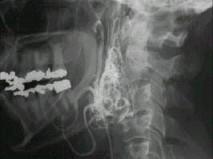

问题 50岁女性,颈部无痛性肿块,逐渐增大,听诊可闻及杂音,DSA检查如图所示,请选择最可能诊断 ( )

选项 A、颈动脉硬化 B、动静脉瘘 C、假性动脉瘤 D、颈动脉夹层 E、颈动脉体瘤

答案 E